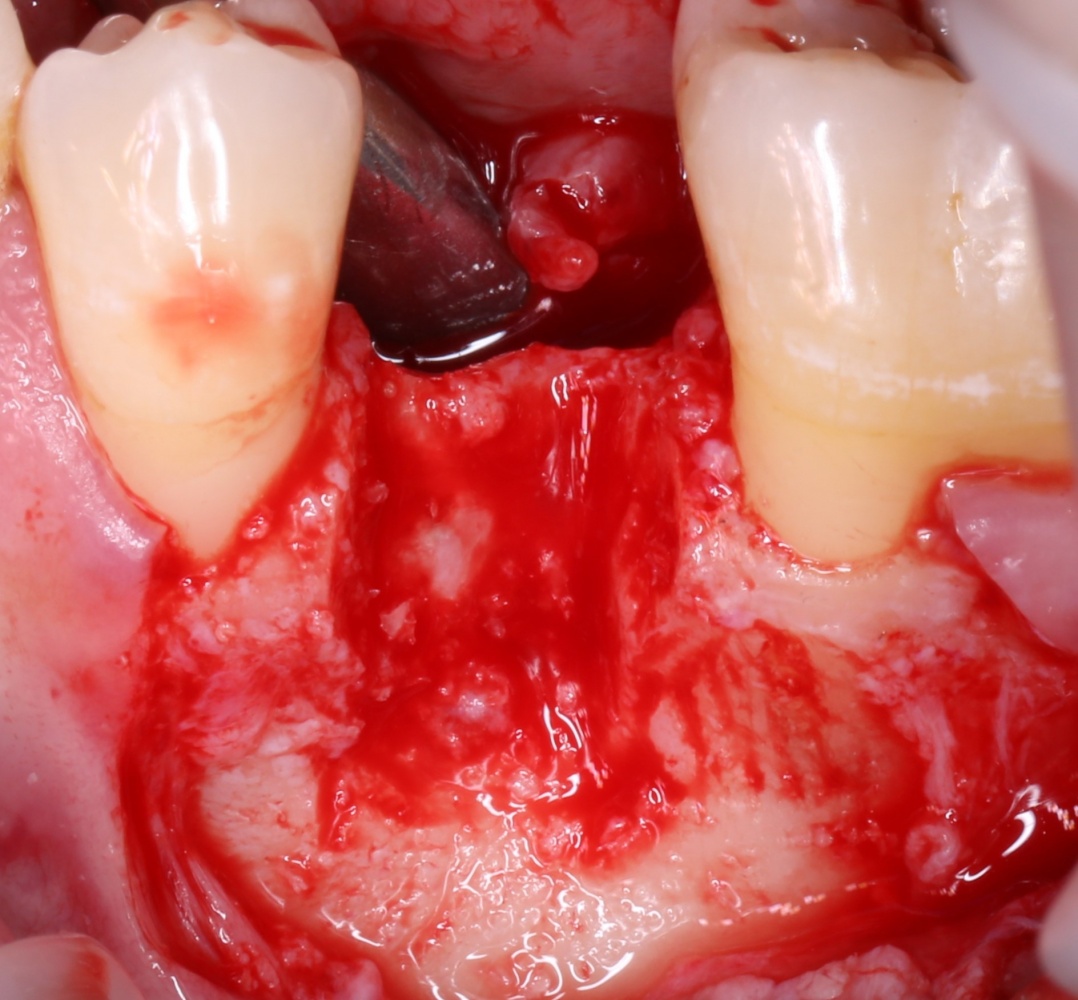

В общем, так и получилось. Уж не помню, почему я наобещал пациентке, что мы поставим ей имплантаты одновременно с остеопластикой. Но я наобещал. И, когда увидел клиническую картину в полости рта:

у меня появились серьезные сомнения, смогу ли я выполнить своё обещание. Вот только не спрашивай меня «Вот чо, сложно было по КЛКТ посмотреть?». Я же не спрашиваю тебя, где ты был в 2013 году, и сделал ли ты домашку. Но, в целом, план операции у нас не поменялся. Как и было оговорено, мы проведем остеопластику с одновременной имплантацией в боковом участке нижней челюсти справа.

Кстати, обрати внимание на ширину альвеолярного гребня (левая картинка). Она чуть меньше 3 мм. Это объясняет, почему я засомневался в возможности установки имплантатов одновременно с остеопластикой. Понятно и без КЛКТ.